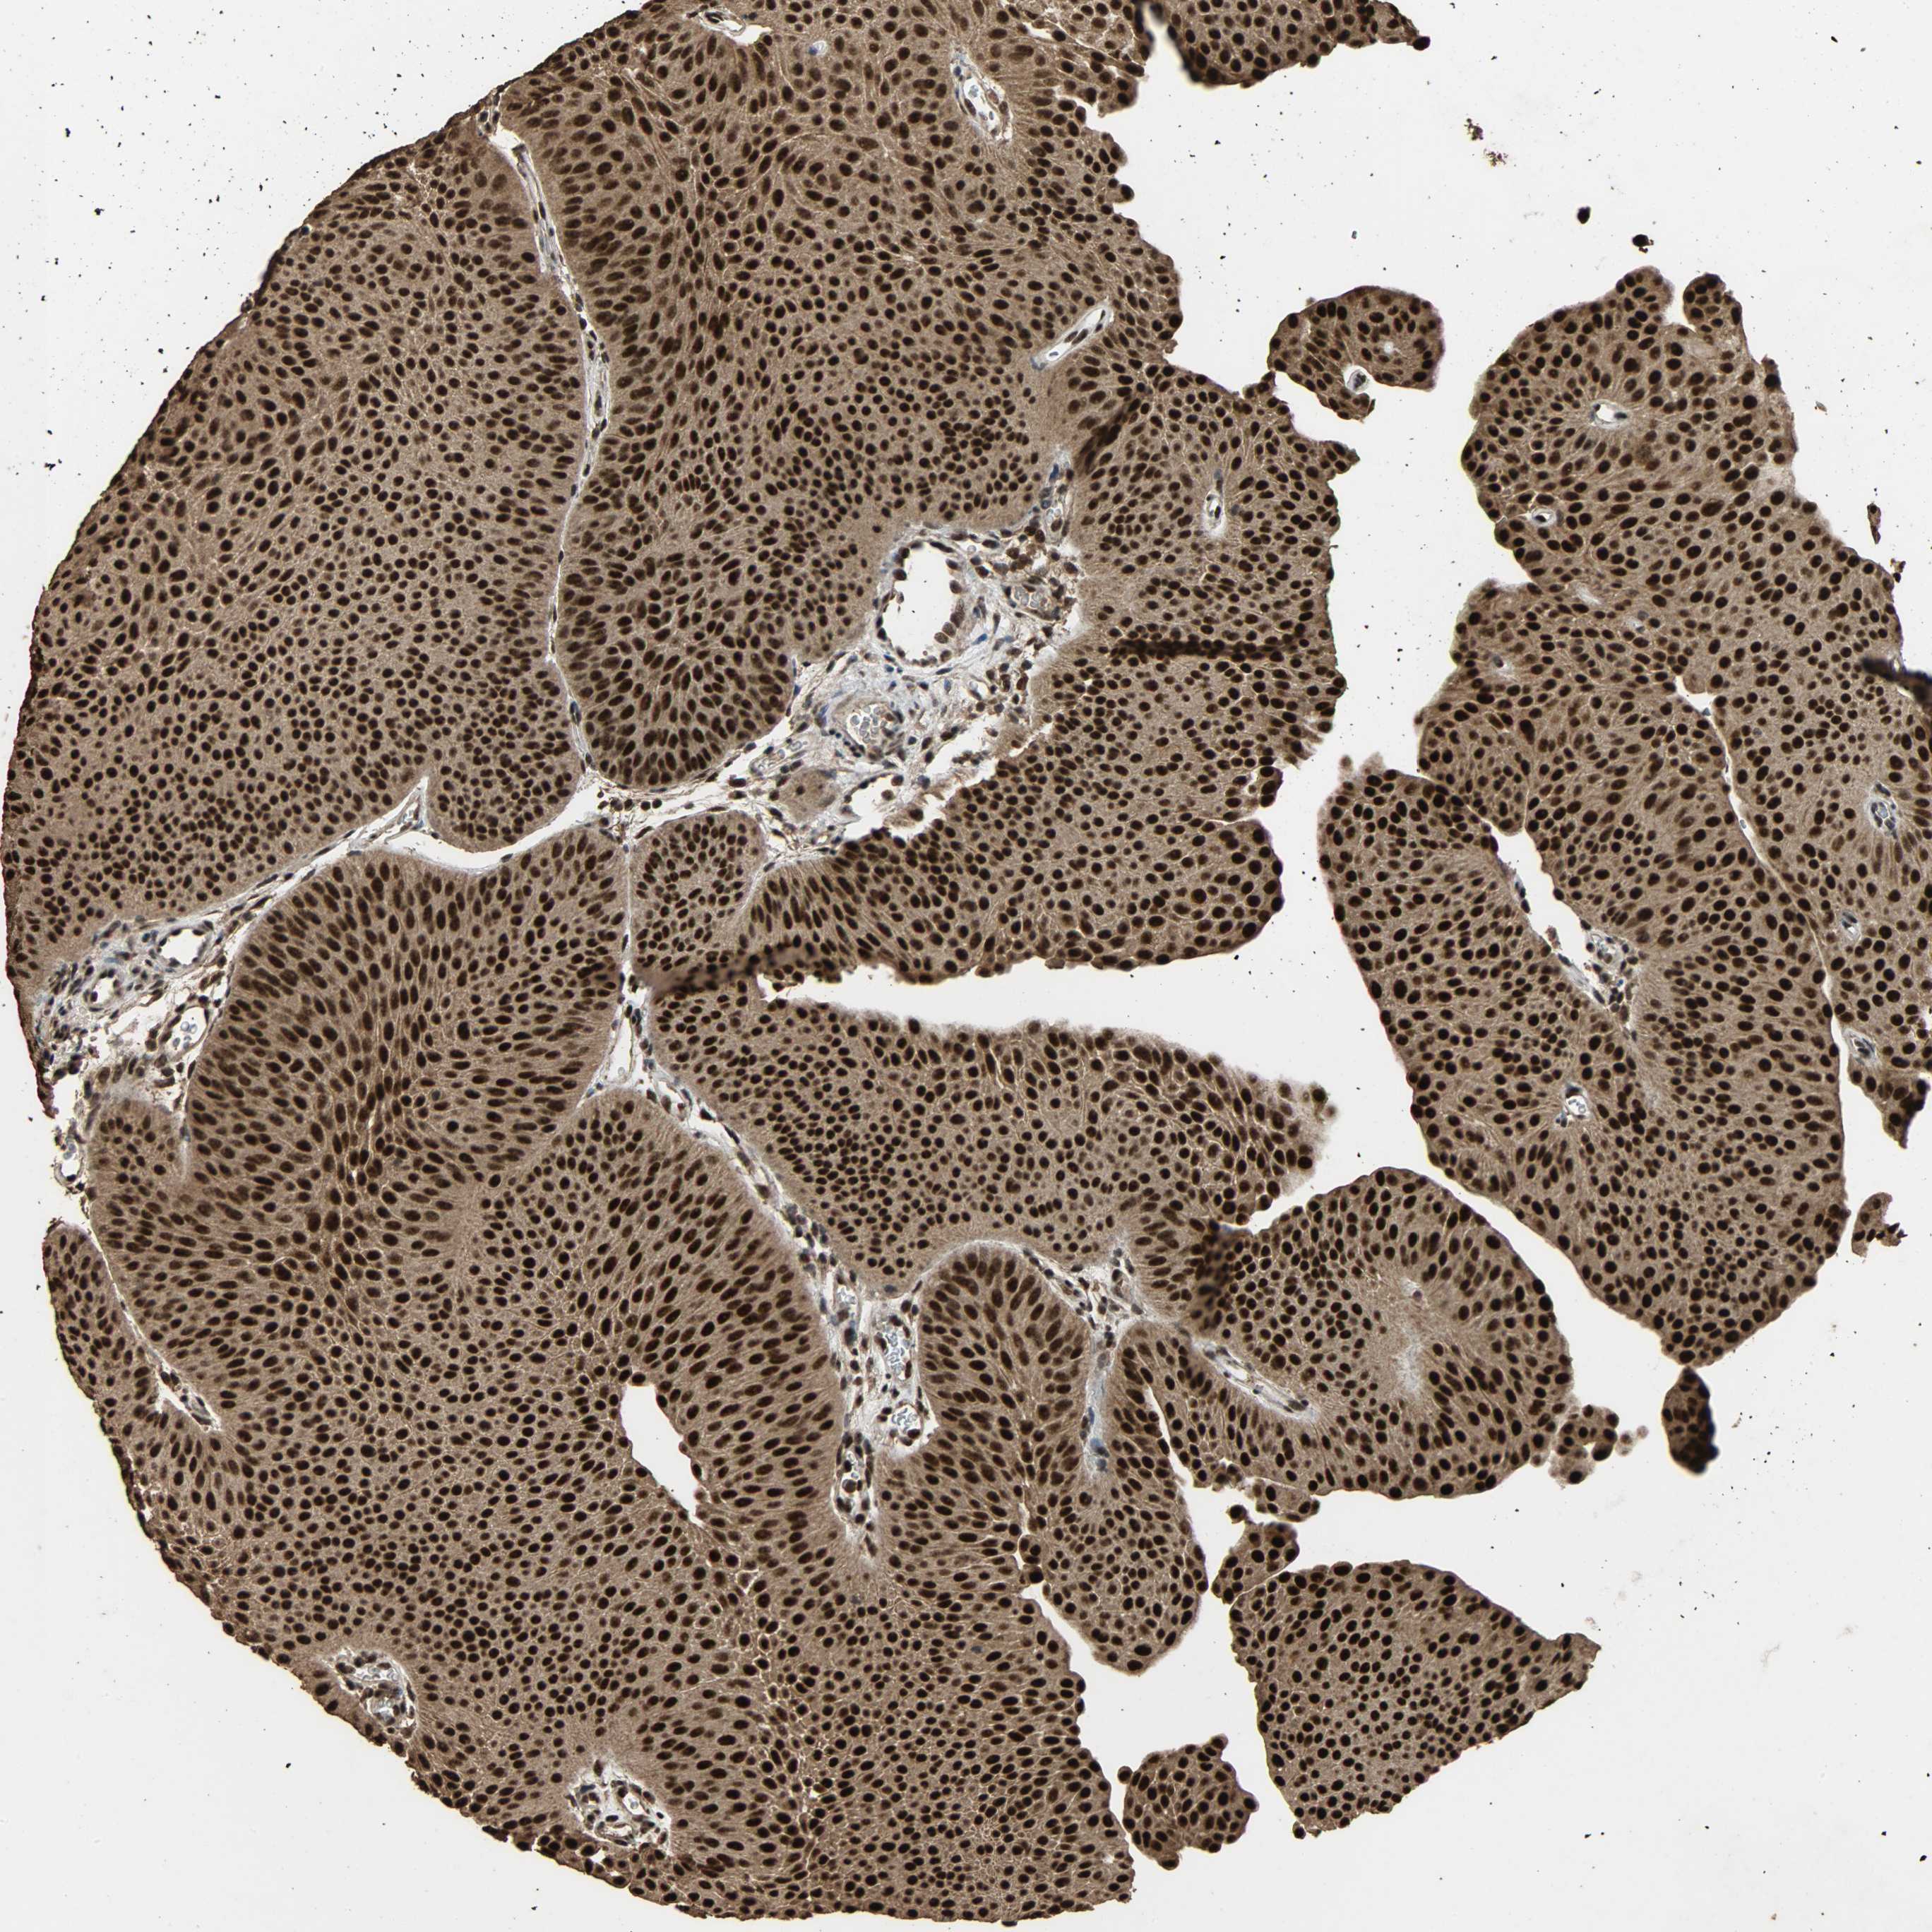

UROTHELIAL CANCER - Protein expressioni

A mouse-over function shows sample information and annotation data. Click on an image to view it in a full screen mode. Samples can be filtered based on level of antibody staining by selecting one or several of the following categories: high, medium, low and not detected. The assay and annotation is described here.

Note that samples used for immunohistochemistry by the Human Protein Atlas do not correspond to samples in the TCGA dataset.

Antibody stainingi

Antibody staining in the annotated cell types in the current human tissue is reported as not detected, low, medium, or high, based on conventional immunohistochemistry profiling in selected tissues. This score is based on the combination of the staining intensity and fraction of stained cells.

Each image is clickable and will lead to virtual microscopy that enables deeper exploration of all samples and also displays staining intensity scores, fraction scores and subcellular localization as well as patient and tissue information for each sample.

Antibody HPA005559

Staining

High

Medium

Low

Not detected

Intensity

Strong

Moderate

Weak

Negative

Quantity

>75%

75%-25%

<25%

None

Location

Nuclear

Cytoplasmic/membranous

Cytoplasmic/membranous,nuclear

Urothelial carcinoma, High grade

Urothelial carcinoma, Low grade